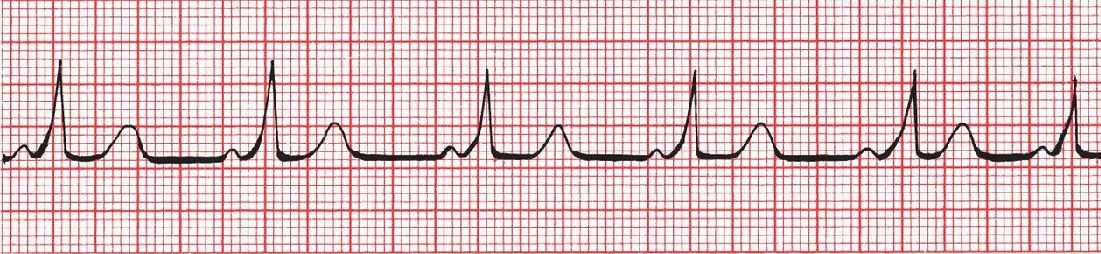

Identify this ECG

WPW syndrome. Current is held up by the normal delay at the AV node but races unimpeded down the bundle of Kent. The EKG shows the short PR interval and delta wave.

PR<0.12

Wide QRS

Delta waves